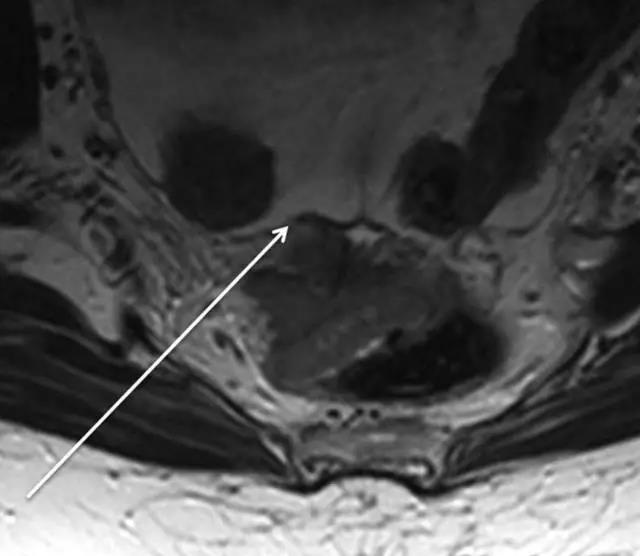

73 岁直肠癌女性,T2 加权轴位图像和相应的线图显示 T3a 肿瘤超出外肌层小于 1 毫米(箭头)。